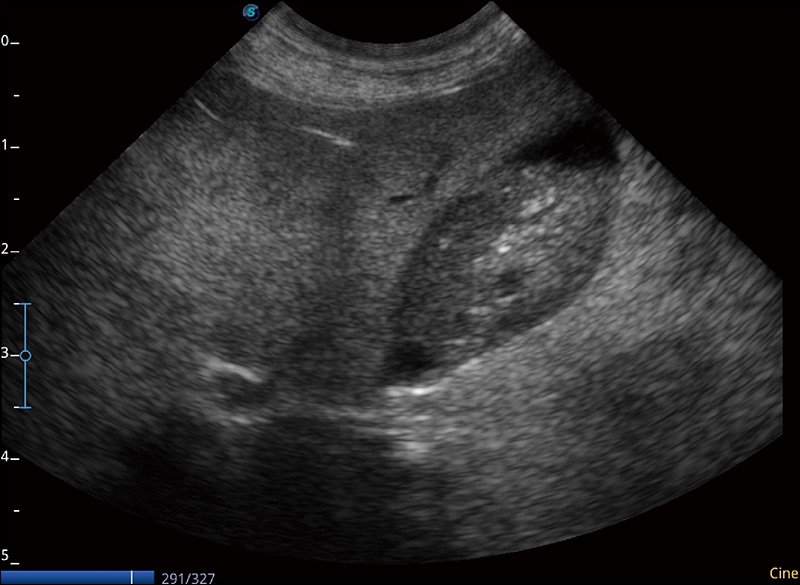

α1卓越的图像质量和便捷的工作流程,使每位宠物医生都能轻松扫查。其全面的兽用应用功能和紧凑型的结构设计,可以满足动物检查的多种需要。专业的预设检查模式和多领域测量软件包有助于为不同类型的动物提供检查, 让宠物医生能够出色的完成工作。

任意波束合成技术

在不牺牲时间分辨率的情况下提供出色的图像

空间复合成像

优化不同角度的图像